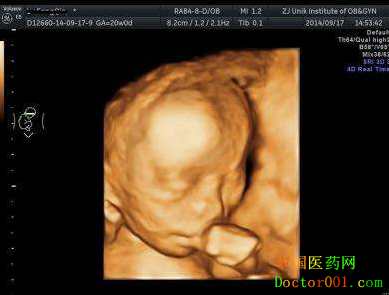

美国GE四维彩超,超越普通四维彩超的局限性,安全无辐射显像更清晰立体,筛查畸形更准确。四维彩超主要用于诊断胎儿先天畸形疾病。如体表,脊柱裂,大脑、肾、心脏、骨骼发育不良等情况,如果发现胎儿发育不良,可以及时采取措施,如果问题比较严重则需要及时终止妊娠。除此之外,还可以看到宫内宝宝的一举一动,满足妈妈的好奇心,同时刻盘留恋,为宝宝保留最珍贵的回忆。 青岛四维彩超排畸检查多少钱?

专家解答:每家医院的资质、设备、专家技术、服务、口碑等不同,其费用也有差异,提供给准妈妈的服务也不一样。 四维彩超的较好时间——孕24-28周 此时胎儿局部结构及运动状态比较清晰,成像效果比较好,可及时发现严重的胎儿畸形、诊断胎儿结构异常。 美国GE-E8四维彩超能筛查哪些畸形? ◇无脑儿:严重胸腹壁缺损伴内脏外翻 ◇单腔心:严重的开放性脊柱裂 ◇严重的脑膨出:致死性软骨发育不全 美国GE四维彩超5大优势